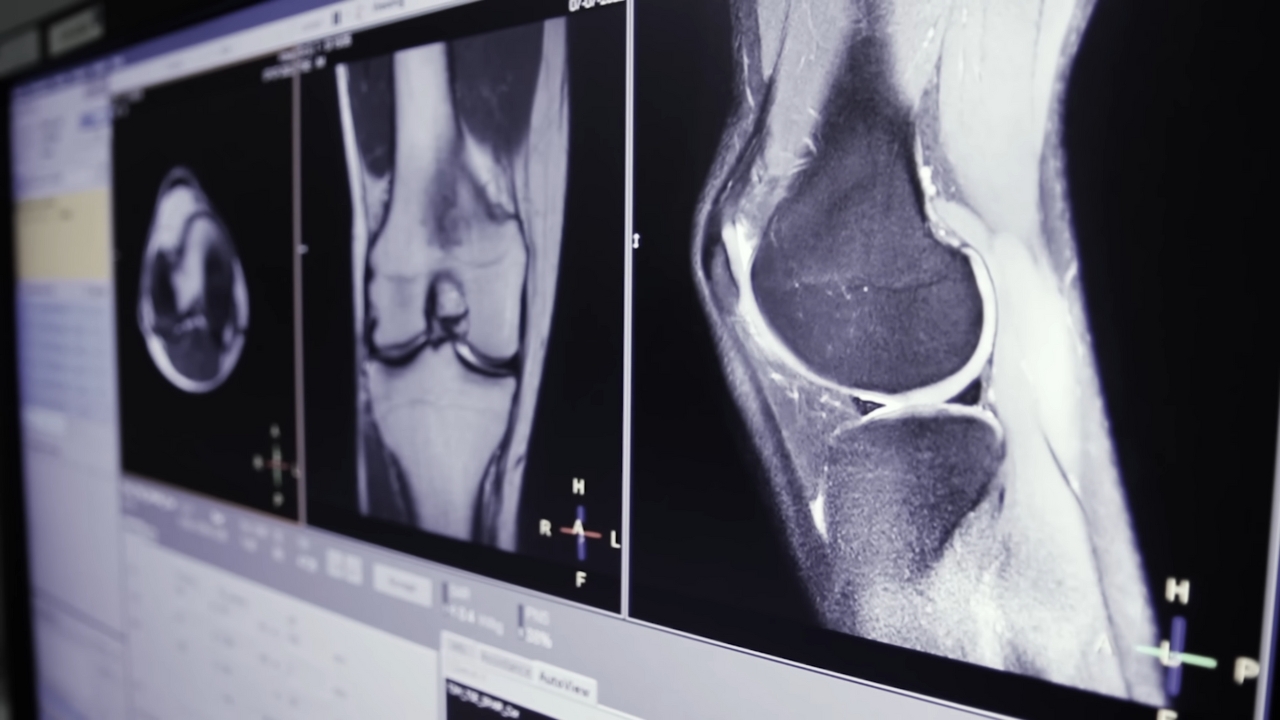

Cartilage plays a crucial role in joint function by providing a smooth, low-friction surface that allows bones to move freely. Unlike many other tissues in the body, cartilage has a very limited ability to heal itself. Once it deteriorates, as often happens with aging or injury, the damage typically becomes permanent.

This progressive loss of cartilage leads to osteoarthritis, one of the most common joint disorders worldwide. The condition causes chronic pain, stiffness, reduced mobility, and, in severe cases, requires joint replacement surgery. Current treatments largely focus on symptom relief rather than true tissue regeneration.